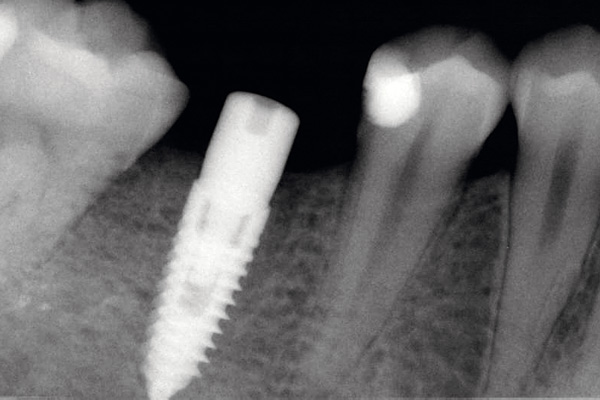

Socket preservation with permamem® - Dr. R. Rannula